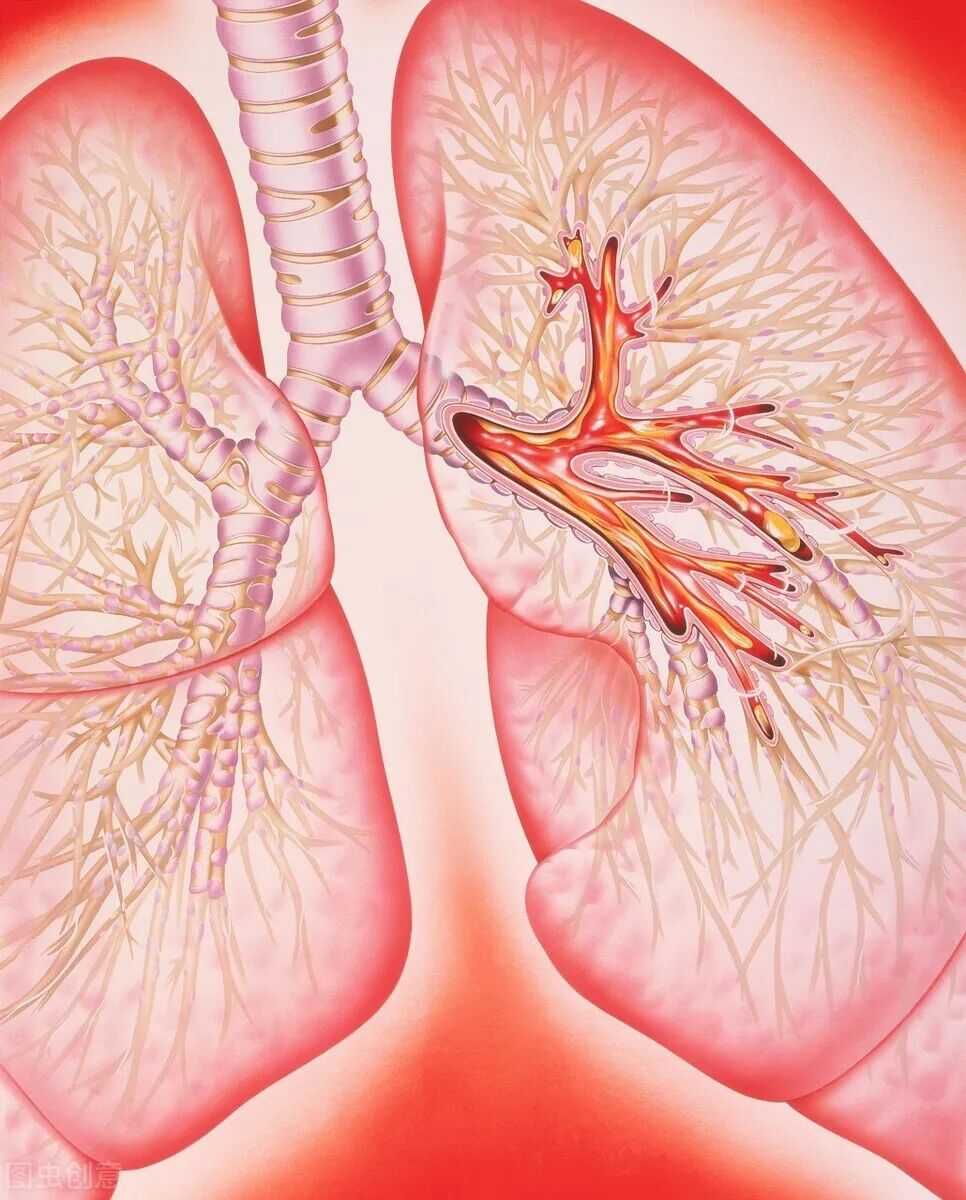

我们首先要了解什么叫:肺气肿。肺脏是由很多肺泡组成的,肺泡是肺脏的基本单位,肺泡很小很小,肉眼看不到,但是肺脏的气体交换工作都是在肺泡里面完成的。

一些经常吸烟的病人,可能会破坏肺泡的结构,导致肺泡的弹性减退,本来肺泡就像一个气球一样,吹气能胀,呼气能瘪的,有弹性的,但如果肺泡结构破坏了,那么这个弹性就差了,肺泡可能会被撑大了,回不来原来的大小,久而久之,气体就会淤积在肥大了的肺泡里面,出不来,进不去(这只是一部分气体,还是有气体能进出自如的),这就是所谓的肺气肿。

每一个肺泡都是这样被撑大了,自然这个肺脏也是被撑大了的,因为肺脏是由肺泡组成的。